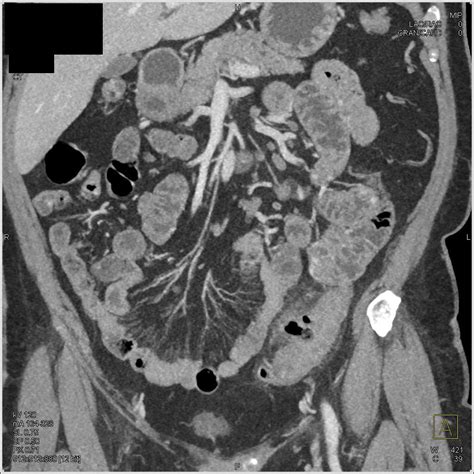

Diagnosing Diverticulitis Sigmoid Colon

Diagnosing diverticulitis sigmoid colon involves a combination of medical history, physical examination, and diagnostic tests. The diagnostic process typically includes:

• Imaging Tests: Imaging tests such as a CT scan or MRI can provide detailed images of the colon and help confirm the diagnosis.